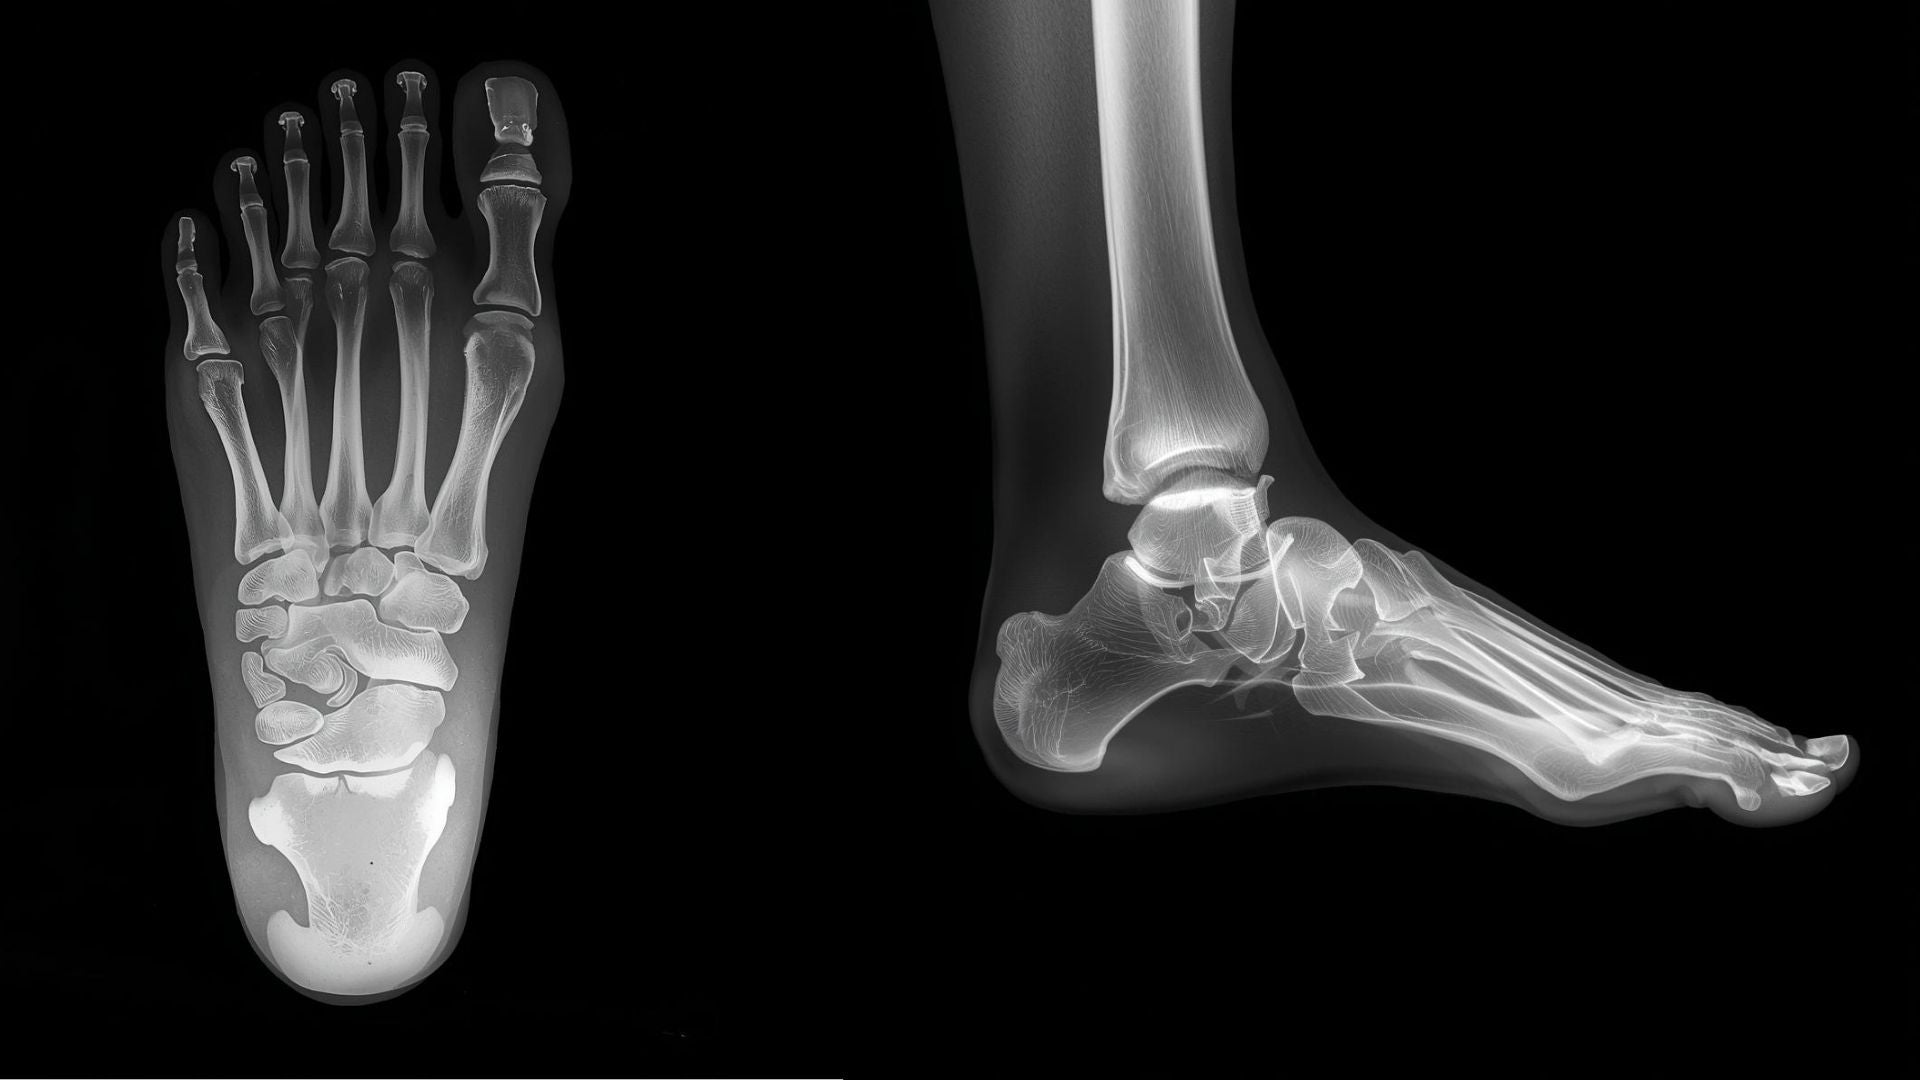

The human foot is an intricate structure, with 26 bones and 33 joints that work together to provide balance, propulsion, and feedback from the ground beneath us (Manganaro, Dollinger, & Nezwek, 2023).

One feature that often goes unnoticed but plays a meaningful role in how the foot functions is toe splay.

Toe splay is the natural ability of the toes to spread when the foot bears weight, helping support balance, stability, and efficient movement.